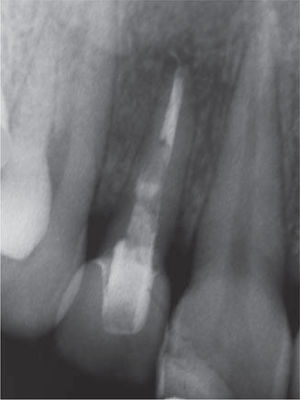

La impresión definitiva tomada a los seis meses de cicatrización con un coping de impresión para cubeta abierta se confeccionó el patrón del pilar con resina acrílica (Pattern Resin GC). Luego fue escaneado con la técnica CAD/CAM (Procera Forte, Nobel Biocare USA) y maquinado en zirconio (Procera óxido de zirconio, Nobel Biocare USA). El asentamiento y la adaptación del pilar se verifica mediante una radiografía periapical (Figura 6). La cerámica fue aplicada sobre el pilar de zirconio pulido, con parámetros de guía incisal y estética similar al diente contralateral. En la parte submucosa del pilar personalizado fue aplicada una capa de 0.5 mm de espesor de cerámica rosada, e.max (Ivoclar Vivadent) acorde con las especificaciones del fabricante simulando el color de la encía de los dientes vecinos (Figura 7). Para lograr compensar el efecto grisáceo de la mucosa, cuando el diente está sin la capa de cerámica rosada en cervical (Figura 8).